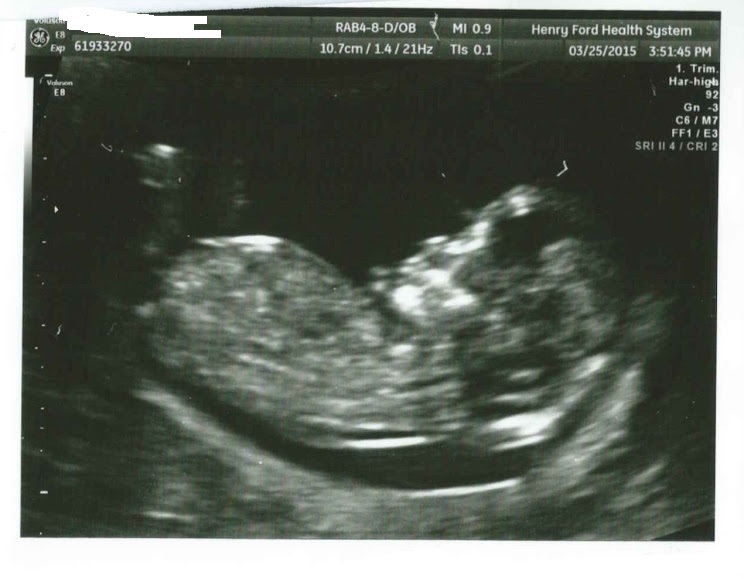

14 weeks, 1 day. I had an abdominal u/s. I've decided to call it my little wiggle worm because it wouldn't stop moving around, and stretching! It took three tries for the tech to capture the heartbeat (148). At one point she managed to get positioned just right to see it's entire front, and not even a second later, it completely turned itself around